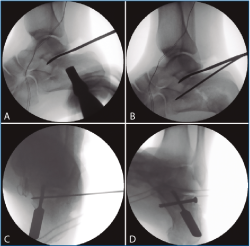

Primero, realizamos limpieza de tejidos blandos y localizamos el flexor hallucis longus (FHL), que será el límite medial de seguridad. Recordamos que, en las fracturas de grado II de Sanders (Figuras 1 y 2), permanece íntegro un gran fragmento anteromedial, mientras que el fragmento posterolateral se desplaza. Tras la limpieza, identificamos la fractura (Figura 3) y movilizamos el fragmento lateral. Luego cambiamos los portales e introducimos el artroscopio por el portal medial, que nos permite acceder hasta el seno del tarso y visualizar el ligamento interóseo talocalcáneo. A través de un pequeño abordaje en la cara lateral del calcáneo reducimos la articulación subastragalina posterior (Figura 4A).

Figura 1. Fractura del calcáneo Sanders IIA.

Figura 2. Fractura del calcáneo Sanders IIB.

En los 4 casos con osteosíntesis percutánea, una vez levantado el fragmento, se realiza una fijación provisional con agujas de 1,8 mm (Figuras 4B y 4C), que podemos emplear, además, para manipular el fragmento y mejorar la corrección. A continuación, se procede a la inserción de los tornillos canulados de 3,5 mm de lateral a medial, solidarizando el fragmento lateral con el anteromedial (Figura 4D). Se debe combinar la visión artroscópica con una visión radiológica que nos confirme la posición y longitud adecuada de los tornillos.

Figura 4. A: control de escopia intraoperatoria (perfil) de la lesión reducida con ayuda de periostotomos; B: control de escopia intraoperatoria (perfil) tras insertar la primera aguja mientras se mantiene la reducción con un periostotomo; C: control de escopia intraoperatoria (axial de calcáneo) tras insertar la primera aguja mientras se mantiene la reducción con un periostotomo; D: control de escopia intraoperatoria (axial de calcáneo) tras colocación del primer tornillo de osteosíntesis.